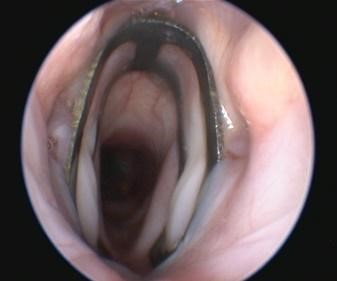

Спустя 2,5 месяца после установки имплантата наблюдается прорастание ткани сквозь перфорации (рис. 1 в) и его полная интеграция в гортани пациента.

Рисунок 1. Результаты клинических испытаний: а) модель имплантата; б) имплантат в гортани мопса непосредственно после установки; в) интеграция имплантата через 9 дней после операции; г) рентгеновский снимок пациента, стрелка указывает на имплантата